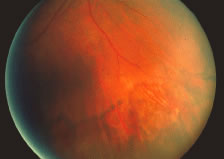

Both herpes simplex virus type 1 and herpes simplex virus type 2 (HSV-1, HSV-2) may cause ARN.20–22 In a single report, CMV particles were identified in and cultured from the retina of an enucleated eye of a nonimmunosuppressed patient suffering from bilateral ARN.23 VZV has been reported most frequently as the viral etiologic agent of ARN.2,3,24–27 We have demonstrated herpesvirus family viral particles in endoretinal biopsy specimens taken from patients in the active stage of the disease who showed an enormous viral load (Fig. 4). These studies, combined with the failure of many enucleated eyes with ARN to demonstrate evidence of viral particles, indicate that the virus is present only in the active stages of the disease and that a gliotic retina will not demonstrate the etiologic agent.28